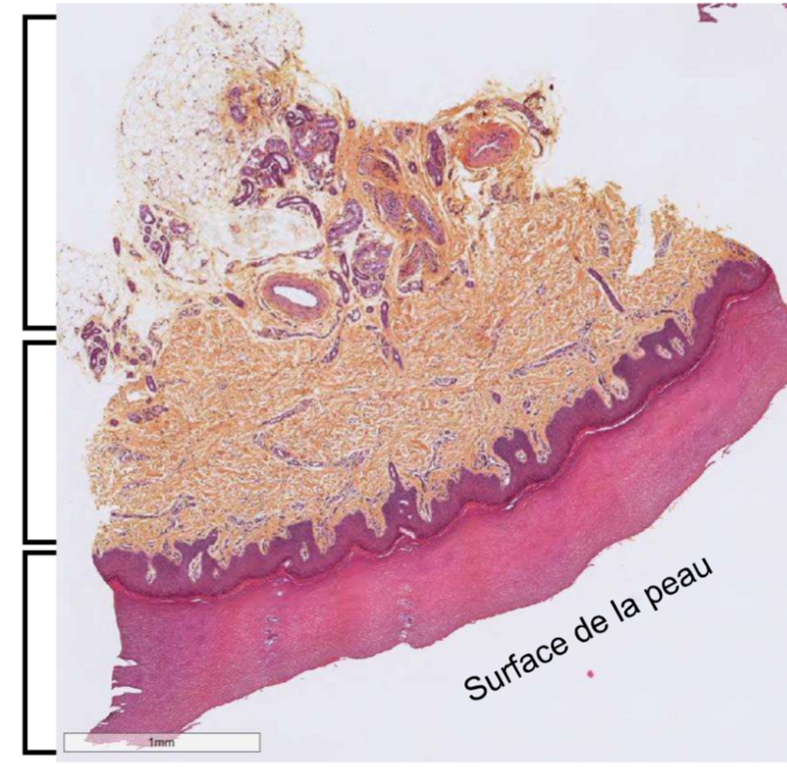

Lame de peau acrale de l’orteil, on observe le derme (on voit a cause du collagène)

de haut en bas:

Identifie les structure et la lame

lame de peau acrale de l’orteil HES, au niveau de l’hypoderme (on voit qu’il y a essentiellement des cell adieuses)

On y retrouve les glandes sudoripares

sécrétrices : cellules plus pales et plus grosses

excrétrices : cellules plus foncées et plus petites

Tissus adipeux en blanc (on enlève les lipides dans la prep)

Fibres de collagène en Orange (safran)

VS